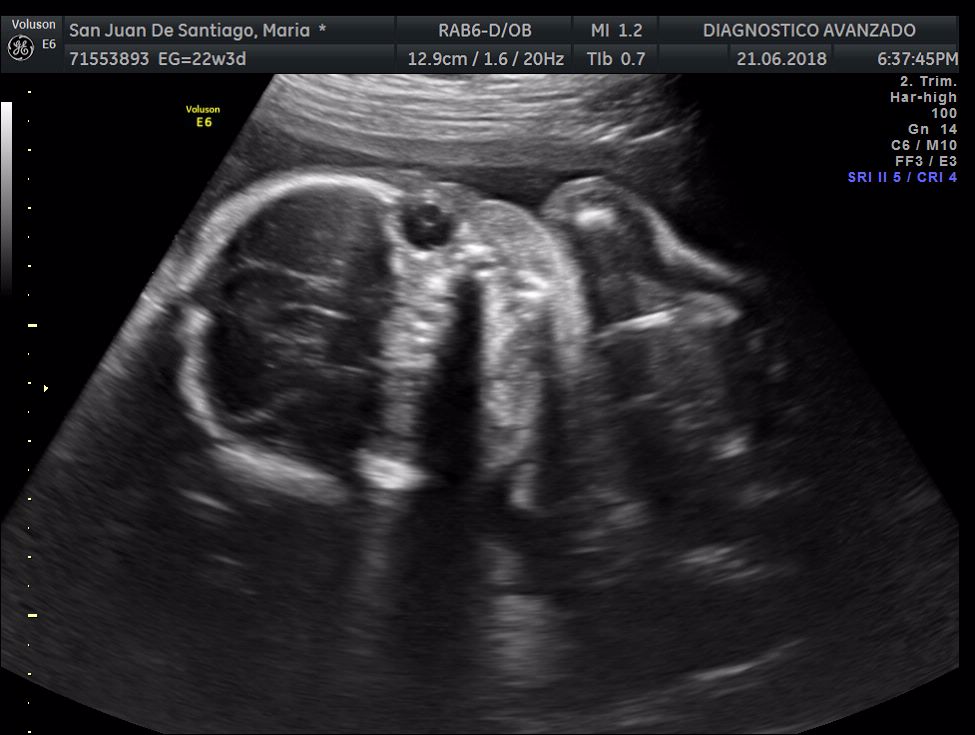

¡Hola a todos! Hoy hemos ido a hacer la tradicional ecografía 3D de la niña, os dejamos todo el material (aunque es un poco demasiado).